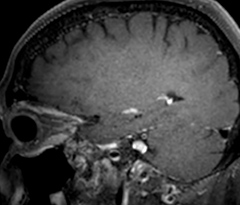

A two year follow-up scan of a CPA meningioma using both Ingenia 3.0T without CS and Ingenia Elition 3.0T with Compressed SENSE allows for a nice comparison to demonstrate the protocol improvements achieved on the Elition: 3D FLAIR has a shortened scan time, improved SNR and still the same spatial resolution. BrainView (3D T1 TSE) has improved spatial resolution and SNR with shortened scan time. For 3D T2 Drive the spatial resolution has been improved. 3D THRIVE used to have an interpolated 0.8 mm slice thickness, but true thickness at 1.6 mm, so that axial slices displayed a decent quality, but reformats were suboptimal. Compressed SENSE is used on Elition to improve spatial resolution and reduce the non-interpolated slice thickness to allow smoothly reformatted images. Total scan time (adding SmartBrain and an additional b2000 diffusion) was 13:19 on Ingenia, and is now reduced to 10:42 on Ingenia Elition.

Ingenia 3.0T (without Compressed SENSE)

3D FLAIR 1.0 x 1.0 x 1.0 mm* 4:24 min.

3D TSE T1w 1.0 x 1.0 x 1.2 mm* 2:40 min.

3D T2w Drive 0.8 x 0.8 x 1.0 mm* 3:05 min.

3D T1w THRIVE 0.8 x 0.8 x 1.6 mm* 1:30 min.

Ingenia Elition 3.0T with Compressed SENSE

3D FLAIR 1.0 x 1.0 x 1.0 mm* 2:50 min.

3D TSE T1w 1.0 x 1.0 x 1.0 mm* 2:10 min.

3D T2w Drive 0.7 x 0.7 x 0.7 mm* 2:52 min.

3D T1w THRIVE 0.7 x 0.7 x 0.8 mm* 1:30 min.

*true voxel size, without interpolation